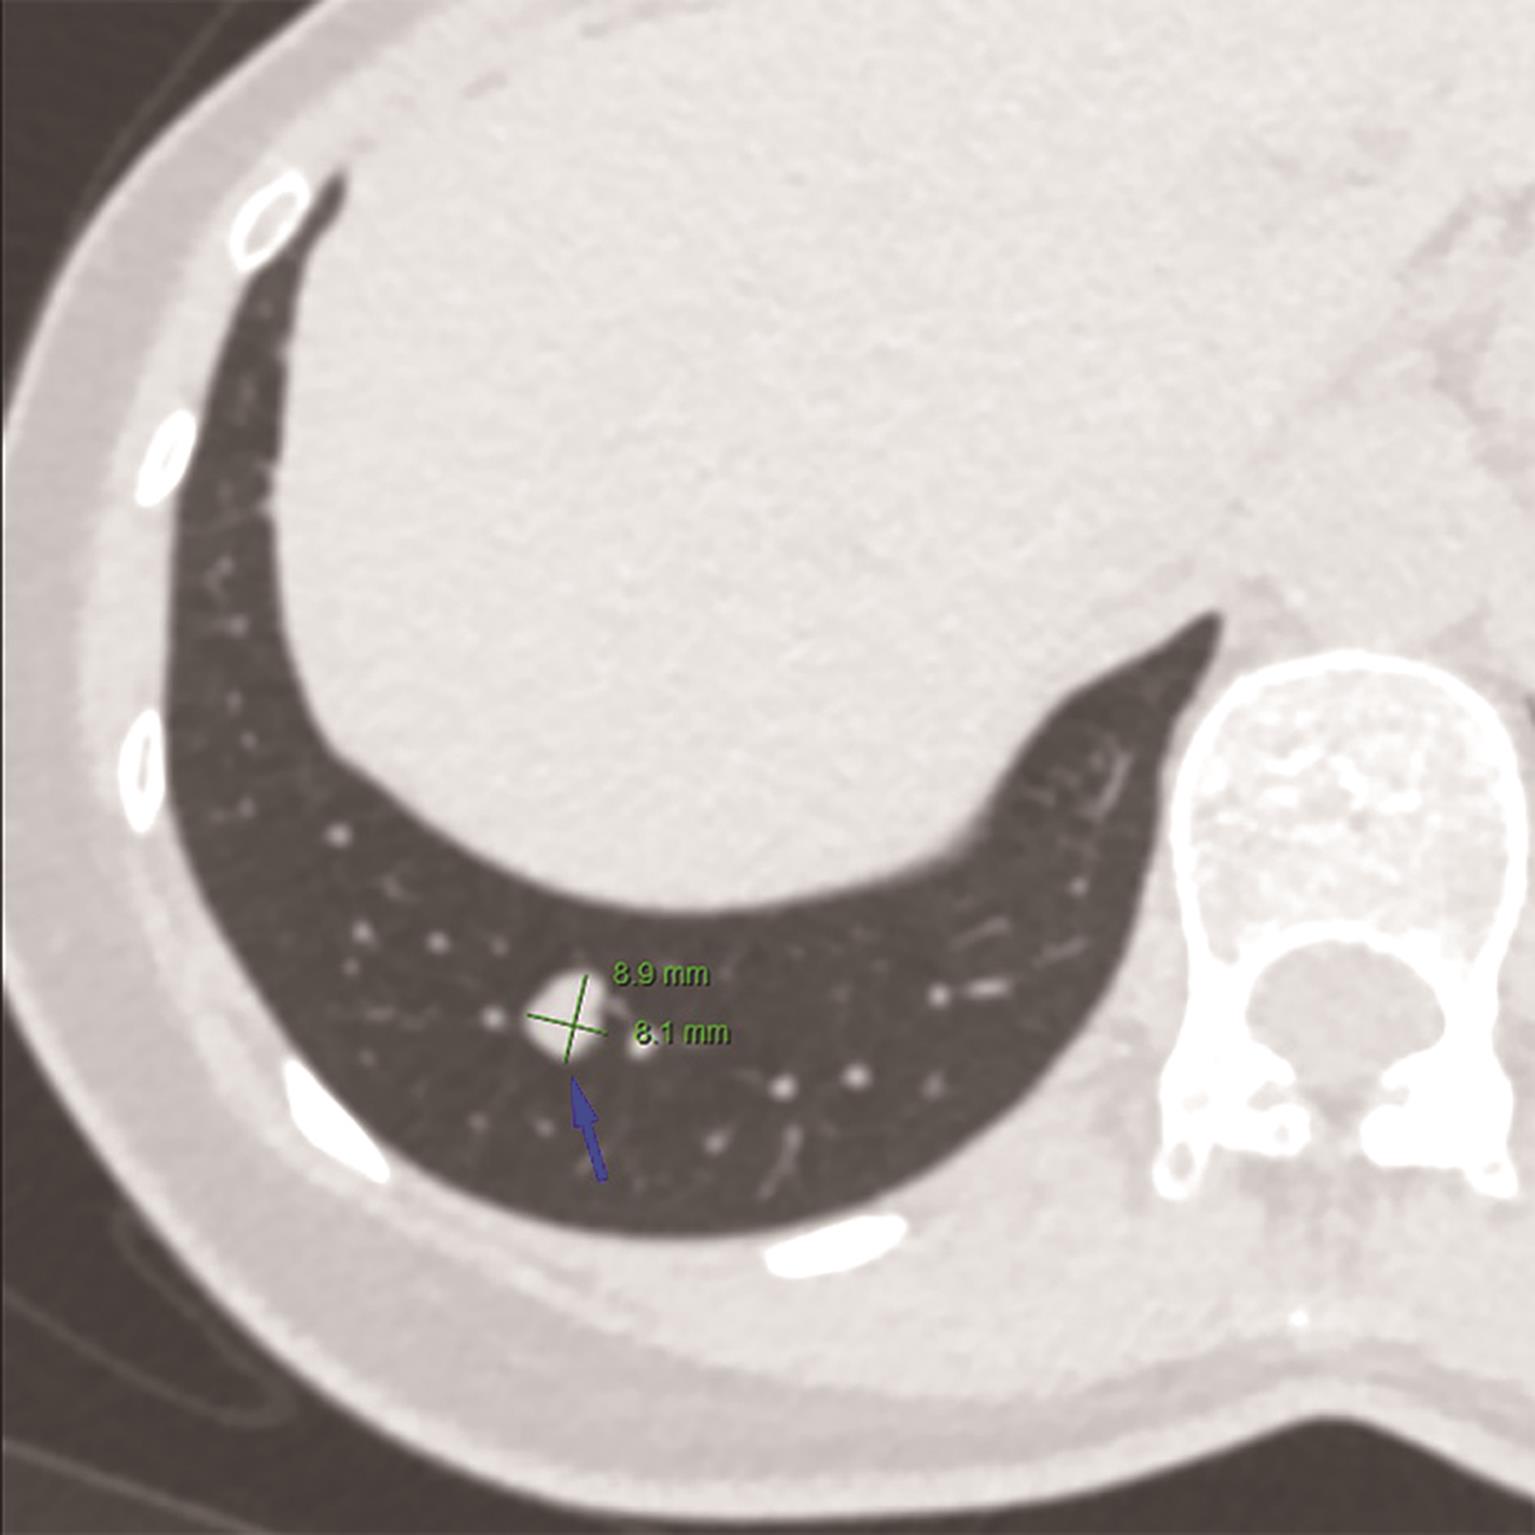

• 肺实性结节半自动体积测量提高观察者间Lung-RADS评分一致性

摘要:目的 研究3D-Slicer软件实性肺结节体积测量对不同观察者在肺部影像报告数据系统(lung CT screening reporting and data system,Lung-RADS)分类一致性中的影响。方法 纳入76例患者中的76个实性结节。由3位放射科医师分别采用手动和3D-Slicer软件半自动体积测量方法获得结节的直径与体积,并转化为相应的Lung-RADS评分,其中2分为阴性,3分及以上为阳性。采用同类相关系数(intraclass correlation coefficient,ICC)及Bland-Altman指数来评价观察者间直径与体积测量的一致性,Kappa分析评价观察者间Lung-RADS评分及阳性/阴性组间的一致性。结果 ICC分析结果显示手动直径测量的一致性(0.994~0.996)明显低于半自动体积测量的一致性(0.997~0.998),同时Bland-Altman指数分析结果显示手动直径测量的偏倚高于半自动体积测量。采用半自动体积测量,能够比手动直径测量明显提高观察者间Lung-RADS评分及阳性/阴性之间的一致性(0.963~0.975及0.957~0.977 vs. 0.833~0.866及0.863~0.892)。结论 3D-Slicer半自动体积测量能够提高实性肺结节观察者间大小测量的一致性,相应的Lung-RADS分类一致性也随之提高。